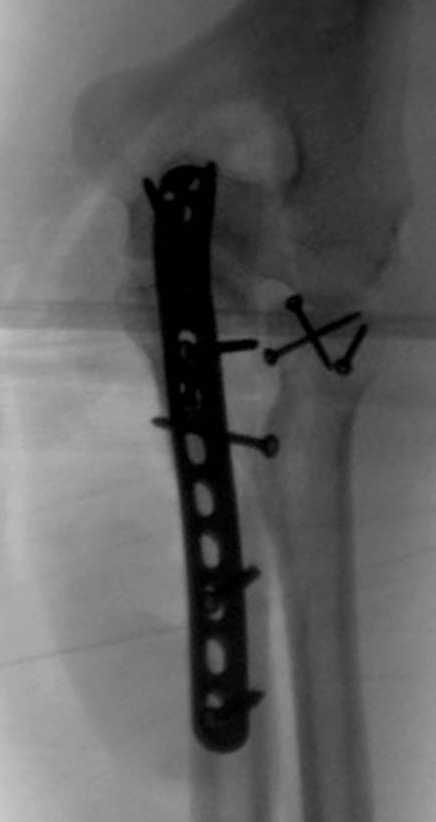

3 вариант

перелом с capitellum humerus и проксимальной трети улна